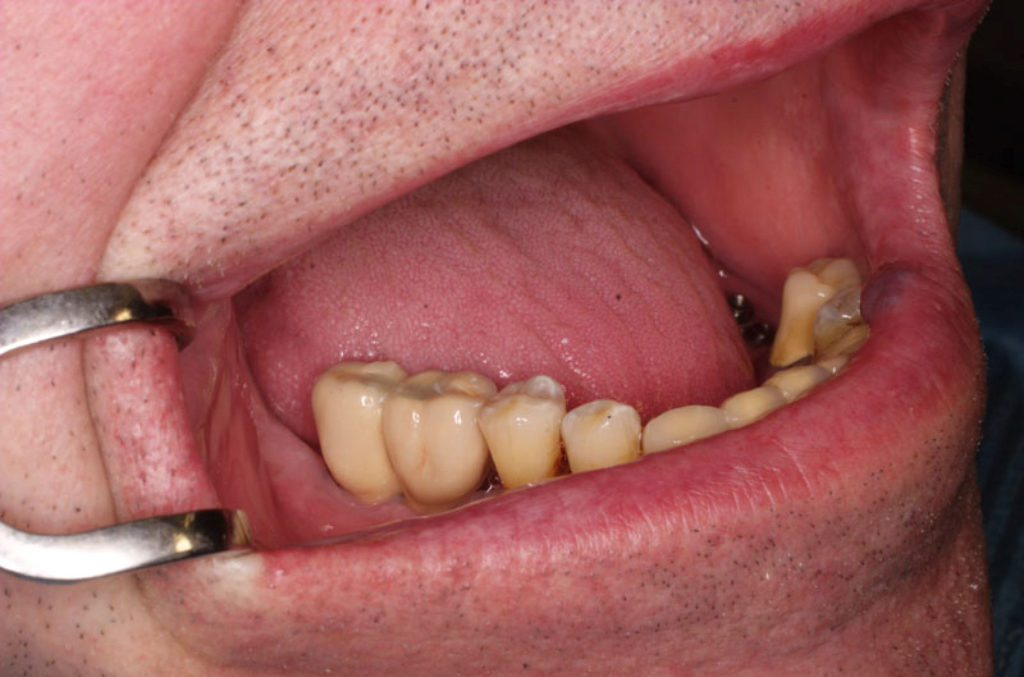

V případě chybění většího počtu zubů v postranních úsecích čelistí je možné ošetření pomocí implantátů, které nahradí ošetření pomocí snímacích náhrad kotvených na zbývajících zubech nebo patře.

Podmínkou je opět dostatečné množství kosti.

Protetické řešení může být pomocí můstku, který je kotvený na implantátech nebo pomocí jednotlivých korunek na implantátech.

V zásadě je možné do těchto můstků zařadit i přirozené zuby, zejména pokud je potřeba tyto zuby ošetřit proteticky – korunkami. Korunky nebo můstky mohou být na implantáty nacementovány nebo přišroubovány.

Zdravé zuby zůstanou zachovány a přitom náhrady jsou pevné, jako na vlastních zubech